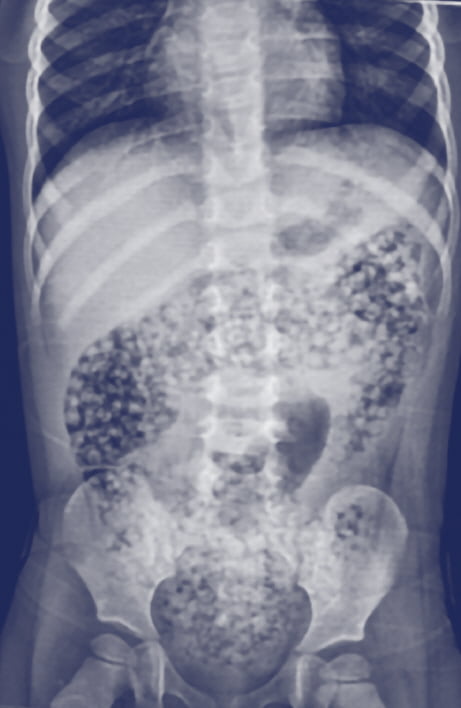

재작년 미국 위스콘신 주에서 10개월 영아가 수정토를 삼켜 장 폐색으로 사망한 사례가 보고됐다. 이에 미국은 수정토를 어린이용품으로 판매하지 못하도록 하는 법안을 추진 중이다.